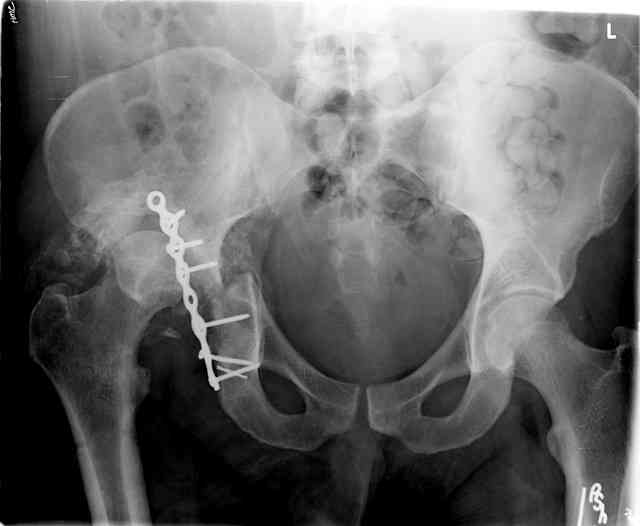

The 2nd example is of a motorcyclist with a transverse fracture-dislocation...he had a closed attempted reduction and placed in traction but the manipulative reduction was not concentric (not unusual for this injury pattern)...so the traction was adjusted to be just enough to disengage the head from the fracture (12#) until he could be cleared for surgery one day after injury...he was treated "urgently" then with a prone KL, clean the fracture, reduce and clamp it, screw it, support with a balanced plate, close, and enjoy...2-3hours, 400cc EBL, blah, blah, blah..

Same with a contoured pelvic reconstruction plate applied and tensioned.

The other oblique reveals the extra-articular implants.... you know the AC screw is extra-articular from the other views.

Routine Fixation

• AC Screw

• PC Neutr Plate

• Others

• The unstable caudal segment is secured by the lower 2 plate screws and the AC medullary screw... always assure that your fixation is sufficient to defeat the instability... part of your prop plan... but assure it before you close... it¹s your last chance... you shouldn't have to be pushing on the hip in contorted ways to determine your fixation stability...you can if that makes you 'comfortable'.

A CT scan will rarely lie to you...reveals your reduction and implants...we use it to assess, teach, grade, and try to get better next time.